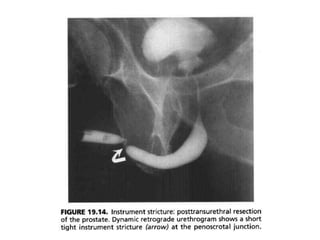

• Instrumentation-related strictures usually occur in the

bulbomembranous region and, less commonly, at the

penoscrotal junction.

• Iatrogenic stricture of the prostatic posterior

urethra (“bladder neck contracture”) usually

occurs after transurethral resection of the

prostate or open radical prostatectomy.